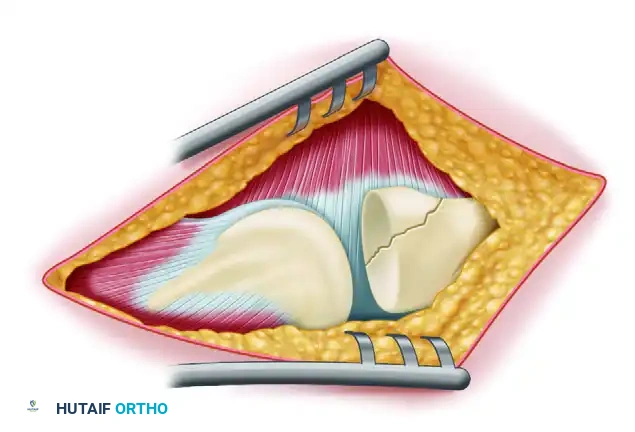

FIGURE 57-67 A: Diagrammatic representation of the lateral approach to the elbow, exposing the radiocapitellar joint and the avulsed lateral structures.

Upon entering the lateral side, the surgeon will typically find the LCL and common extensor origin completely avulsed from the lateral epicondyle.

FIGURE 57-66 A: Intraoperative view of a “terrible triad” injury. Note the characteristic stripping of the lateral collateral ligament complex from the distal humerus. A portion of the common extensor origin/lateral ligament complex is hanging down from the bare lateral condyle. The coronoid fragment is trapped in the joint (arrowhead), and the defect in the radial head can be seen behind it.

The joint is irrigated, and fracture hematoma is cleared. If the radial head is irreparably comminuted, it is excised at this stage. Crucially, the radial head prosthesis is not inserted yet. The void left by the excised radial head provides unparalleled visualization of the deep, anteriorly located coronoid process.